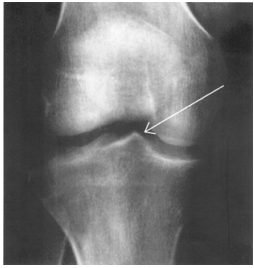

40 如圖所示,箭頭所指之結構為下列何者?

(A)骨刺 (B)種子骨 (C)髁間嵴 (D)鈣化之肌腱